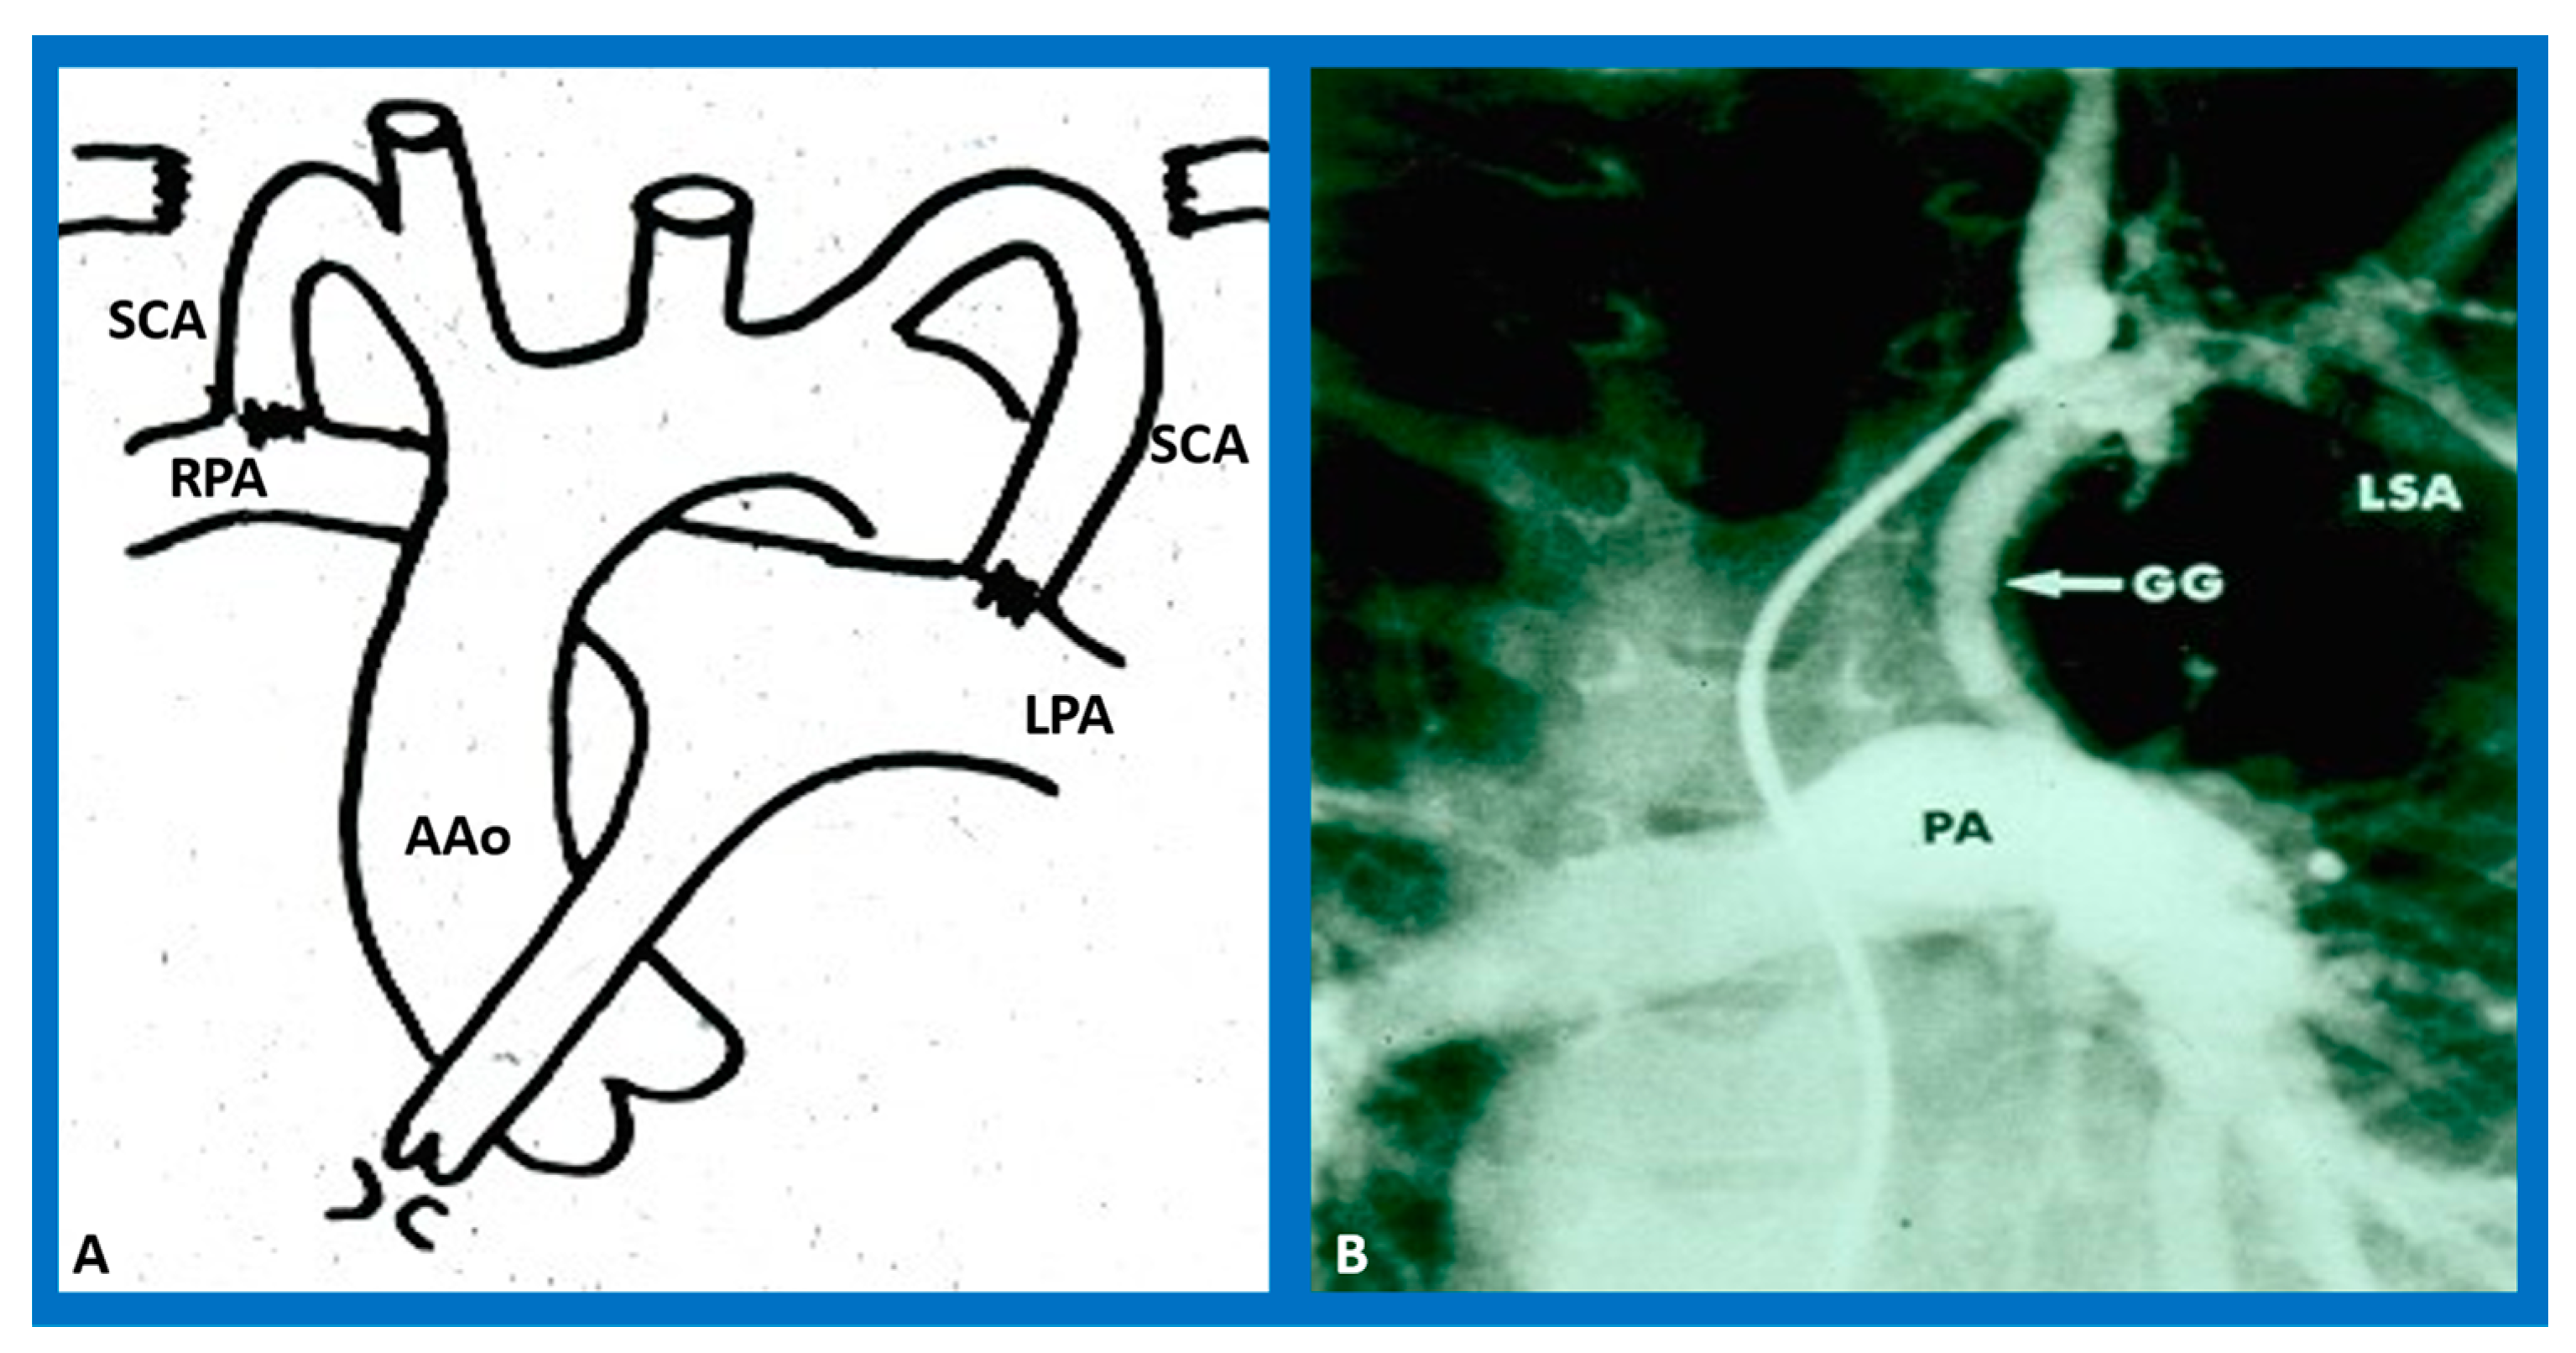

- Blalock, A.; Taussig, H.B. The surgical treatment of malformations of the heart in which there is pulmonary stenosis or atresia. J. Am. Med. Assoc. 1945, 128, 189–194. [Google Scholar] [CrossRef]

- De Leval, M.R.; McKay, R.; Jones, M.; Stark, J.; Macartney, F.J. Modified Blalock-Taussig shunt: Use of subclavian orifice as a flow regulator in prosthetic systemic-pulmonary artery shunts. J. Thorac. Cardiovasc. Surg. 1981, 18, 112–119. [Google Scholar] [CrossRef]

- Li, D.; Wang, Y.; Lin, K.; An, Q. Modified Blalock-Taussig shunt: A single-center experience and follow-up. Heart Surg. Forum 2020, 23, E053–E057. [Google Scholar] [CrossRef]